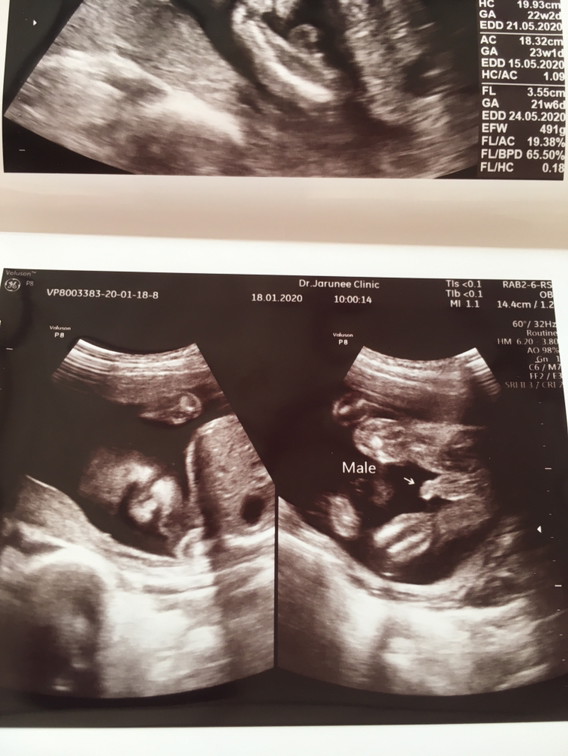

ใบซาวด์

ขอดูใบซาวด์แม่เพศ ชาย หญิง หน่อยค่ะ

ชายจร้า

ลูกชายค่ะ

ผช จร้า

ผช.จ้าา

ผช จ้าา

ชายค่ะ

ชายจ้า